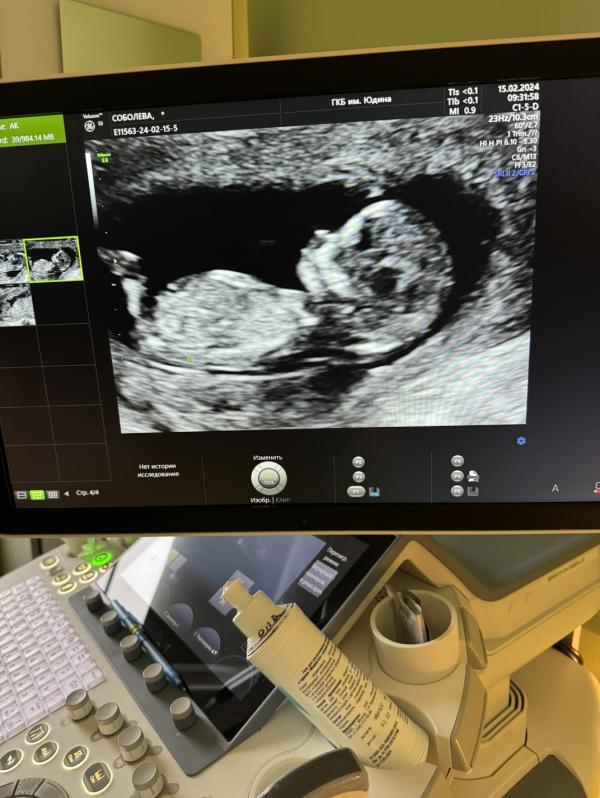

Сказали все замечательно!Немного опережает.Сказали похожа на девочку)8 апреля,скажут точнее

Какой профиль чудесный! Классное фото получилось!